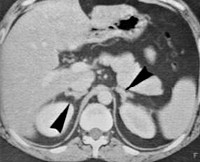

Врожденная гиперплазия надпочечников. Увеличение объема надпочечников связано с дефектом ферментов стероидогенеза в зоне коры головного мозга, что приводит к компенсаторному росту органов для устранения гормонального дефицита. Это проявляется как признаки гиперандрогении у детей обоего пола, в результате чего наружные половые органы развиваются ненормально. Характерно также нарушение водно-солевого обмена и регуляции артериального давления с тенденцией к его снижению. Врожденная гиперплазия надпочечников диагностируется на основании лабораторных данных. Проводится заместительная гормональная терапия и хирургическая коррекция наружных половых органов.

Первичный диагноз ставится во время УЗИ беременных женщин. Иногда во время первого или (чаще) второго акушерского УЗИ вы можете заметить аномальное развитие половых органов. Если есть подозрение на врожденную гиперплазию надпочечников, могут быть проведены дополнительные лабораторные анализы для определения уровня гормонов и концентрации различных ферментов стероидогенеза надпочечников. Ранняя диагностика позволяет специалистам определить другие тактики ведения беременности, а также начать терапевтические мероприятия еще до родов.